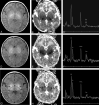

Background: Although the imaging, spectroscopic, and diffusion characteristics of brains of infants with neonatal encephalopathy have been described, the time course during which these changes evolve is not clear. The results of sequential MR imaging studies--including anatomic MR imaging, proton MR spectroscopy, and diffusion tensor imaging (DTI)--of 10 patients enrolled prospectively in a study of neonatal encephalopathy are reported to help to clarify the time course of changes in different brain regions during the first 2 weeks of life.

Methods: Ten neonates were prospectively enrolled in a study of the evolution of MR findings in neonatal encephalopathy and were studied 2 (8 patients) or 3 (2 patients) times within the first 2 weeks of life. The MR examination included spin-echo T1 and T2-weighted images, DTI, and long echo time (288 milliseconds) proton MR spectroscopy. Diffusion parameters (diffusivity [D(av)], fractional anisotropy [FA], and individual eigenvalues) were calculated for 10 1-cm2 regions of interest in each hemisphere that were placed based on anatomic landmarks. D(av) and FA were then measured manually in the same areas on a workstation. Metabolite ratios (NAA/Ch, Cr/Ch, Cr/NAA, Lac/Ch, and Lac/NAA) were calculated in 7 regions of interest. Imaging appearance, diffusion parameters, and metabolite ratios were then evaluated longitudinally (comparing with other studies on the same patient at different times) and cross-sectionally (comparing all studies performed on the same postnatal day).

Results: In most of the patients a characteristic evolution of DTI and MR spectroscopy parameters was seen during the first 2 weeks after birth. Although the anatomic images were normal or nearly normal on the first 2 days after birth in most patients, abnormalities were detected on DTI (both visually and by quantitative interrogation of D(av) maps) and proton MR spectroscopy (abnormal metabolite ratios). These parameters tended to worsen until about day 5 and then normalize, though in several patients abnormal metabolite ratios persisted. Of interest, as areas of abnormal diffusivity pseudonormalized within one region of the brain they would develop in other areas. Therefore, the pattern of injury looked very different when imaging was performed at different times during this evolution.